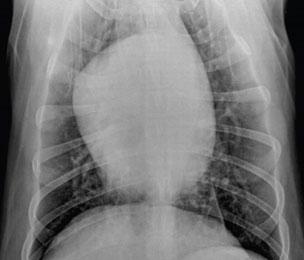

•AbdominalUltrasound

•“SwissCheese”liver(mayormay notbepresent)

•Mayalternativelydetect glucagonomasorother pancreaticorhepatictumors